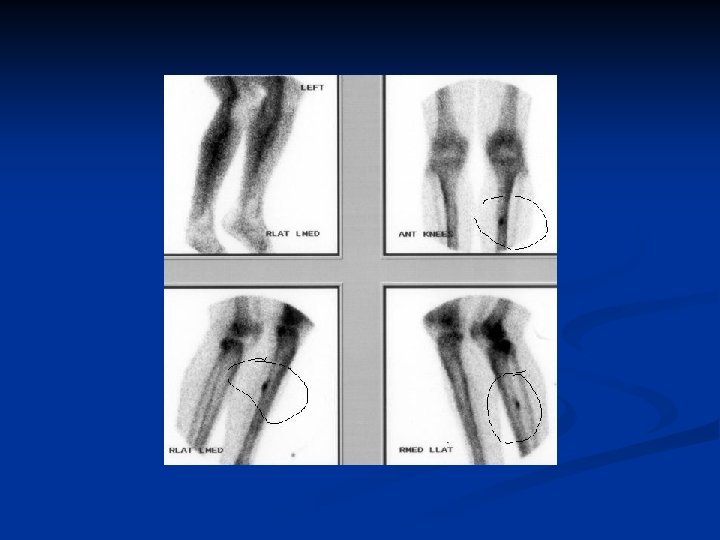

2. Fatigue or stress fractures: Is the one occurring in the normal bone of a healthy patient due to repetitive stress rather than single traumatic evidence. n Most common sites affected pubic rami , femoral neck , tibial shaft especially in trainee and athletes , distal fibula , metatarsals especially the second. n

Investigations: n n n XR of other regions accordingly. Blood investigation: always should include full blood count, ESR , and according to the disease. Urine examination : for RBCs , Bence – Jones protein for m. myeloma. Scanning: whole body scan to exclude other deposits. Biopsy: some times essential for uncertain lesions. And if open reduction done biopsy can be taken easily.

Special imaging Some times the fracture not seen in usual XR so do: v Tomography as in spine. v CT v MRI may be the only way to show whether the fractured vertebra compress the spinal cord. v Radioisotope scan is helpful in stress fractures.